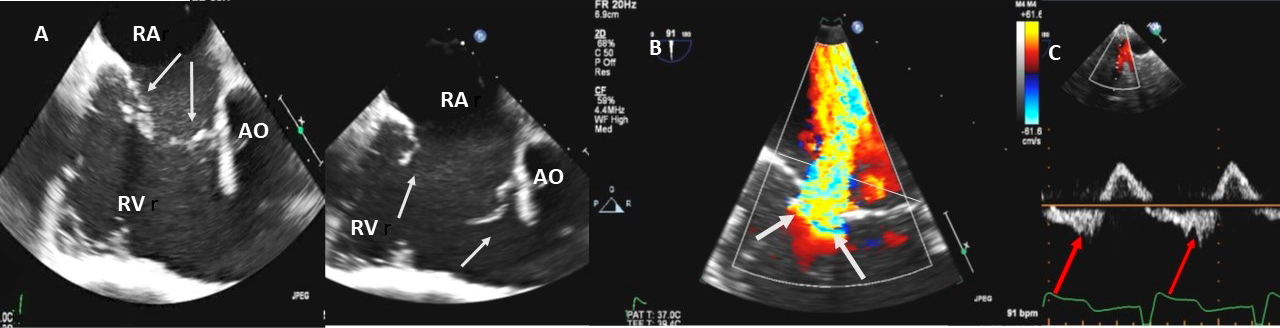

Fig. 4.Functional Tricuspid regurgitation. (A) TEE mid esophageal inflow-outflow view shows a dilated RV and tricuspid annulus (white arrows). (B) TEE 4 chamber view color Doppler showing centrally directed severe tricuspid regurgitation with PISA (white arrows). (C) PW Doppler showing systolic hepatic flow reversal, which suggests severe TR (red arrows). RA; right atrium; RV, right ventricle; AO, aorta.

Examples of valvular injury directly from implantable cardioverter-defibrillator lead placement (Fig. 5A–C) or a permanent pacemaker (Fig. 6A–C) or endomyocardial biopsy in cardiac transplant recipients (Fig. 7A,B) are shown.

Fig. 5.Tricuspid regurgitation induced by pacemaker lead impingement. (A) 3D transthoracic echo showing and dilated RV, RA and anterior leaflet impingement by the device lead (red arrows). (B) Inspiratory systolic hepatic flow reversal (red arrows), which suggests severe TR. (C) Apical four chamber view showed severe tricuspid regurgitation. RA, right atrium; RV, right ventricle; AV, aortic valve; AL, anterior leaflet; PL, posterior leaflet; SL, septal leaflet; MV, mitral valve.

Fig. 6.Tricuspid regurgitation induced by pacemaker lead valve perforation. (A) Transthoracic 2D 4 chamber view showing pacemaker lead going through the TV leaflet (white arrow) and causing TR. (B) 3D enface view of the TV from the right atrial perspective showing the pacemaker lead going through the margin of the septal leaflet (SL) of the TV (white arrow). (C) 3D color Doppler view of the TV from the atrial perspective showing origin of TR at the site of leaflet perforation. MV, mitral valve; AV, aortic valve; PL, posterior leaflet; AL, anterior leaflet

Fig. 7.Tricuspid regurgitation following endomyocardial biopsy. (A) Flail tricuspid valve leaflet that occurred as a complication of an endomyocardial biopsy. Apical 4 chamber view showed flail septal leaflet (SL, septal leaflet; AL, anterior leaflet). (B) Color-flow Doppler imaging. Eccentric, anteriorly directed jet of tricuspid regurgitation (SL, septal leaflet of tricuspid valve; AL, anterior leaflet of tricuspid valve).